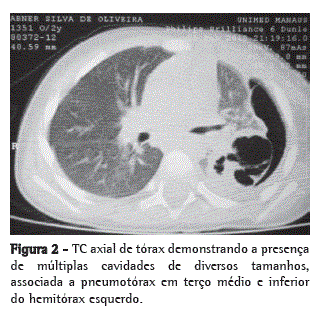

Quanto às complicações cirúrgicas pós-operatórias, a complicação mais comum foi o escape aéreo persistente por FBP, observado em 4 pacientes (20%) que foram submetidos à segmentectomia. As outras complicações foram, em 1 paciente (5%) cada, pneumatocele, empiema e flebite em membro superior esquerdo. Não foram encontradas complicações cirúrgicas pós-operatórias em 9 pacientes (45%), recebendo alta, em média, no 10º dia pós-operatório (Tabela 2). As Figuras 1, 2 e 3 exemplificam, respectivamente, os achados radiológicos, tomográficos e operatórios em 1 paciente submetido à ressecção do segmento seis.

A persistência de febre, dor torácica, sinais de desconforto respiratório, piora do quadro clínico ou surgimento de novas complicações secundárias à pneumonia na vigência de antibioticoterapia otimizada podem sugerir necrose pulmonar.(6,8,9) Nesses pacientes, está indicada a realização da TC axial torácica, mesmo se a radiografia de tórax não demonstre nenhuma anormalidade, pois essa é pouco sensível e raramente apresenta algum achado precoce característico das complicações necróticas.(8-10) Os achados na TC axial de tórax mais característicos na PN são o aparecimento de áreas de menor densidade e cavidades múltiplas, com ou sem níveis hidroaéreos que podem coalescer e formar uma única e extensa cavidade.(10,11) Nesta série, todos os pacientes foram submetidos à TC axial de tórax, e o achado mais comum foi a presença de múltiplas cavidades. Em 75% dos pacientes, a radiografia torácica realizada antes da TC axial já evidenciava a presença dessas cavidades.